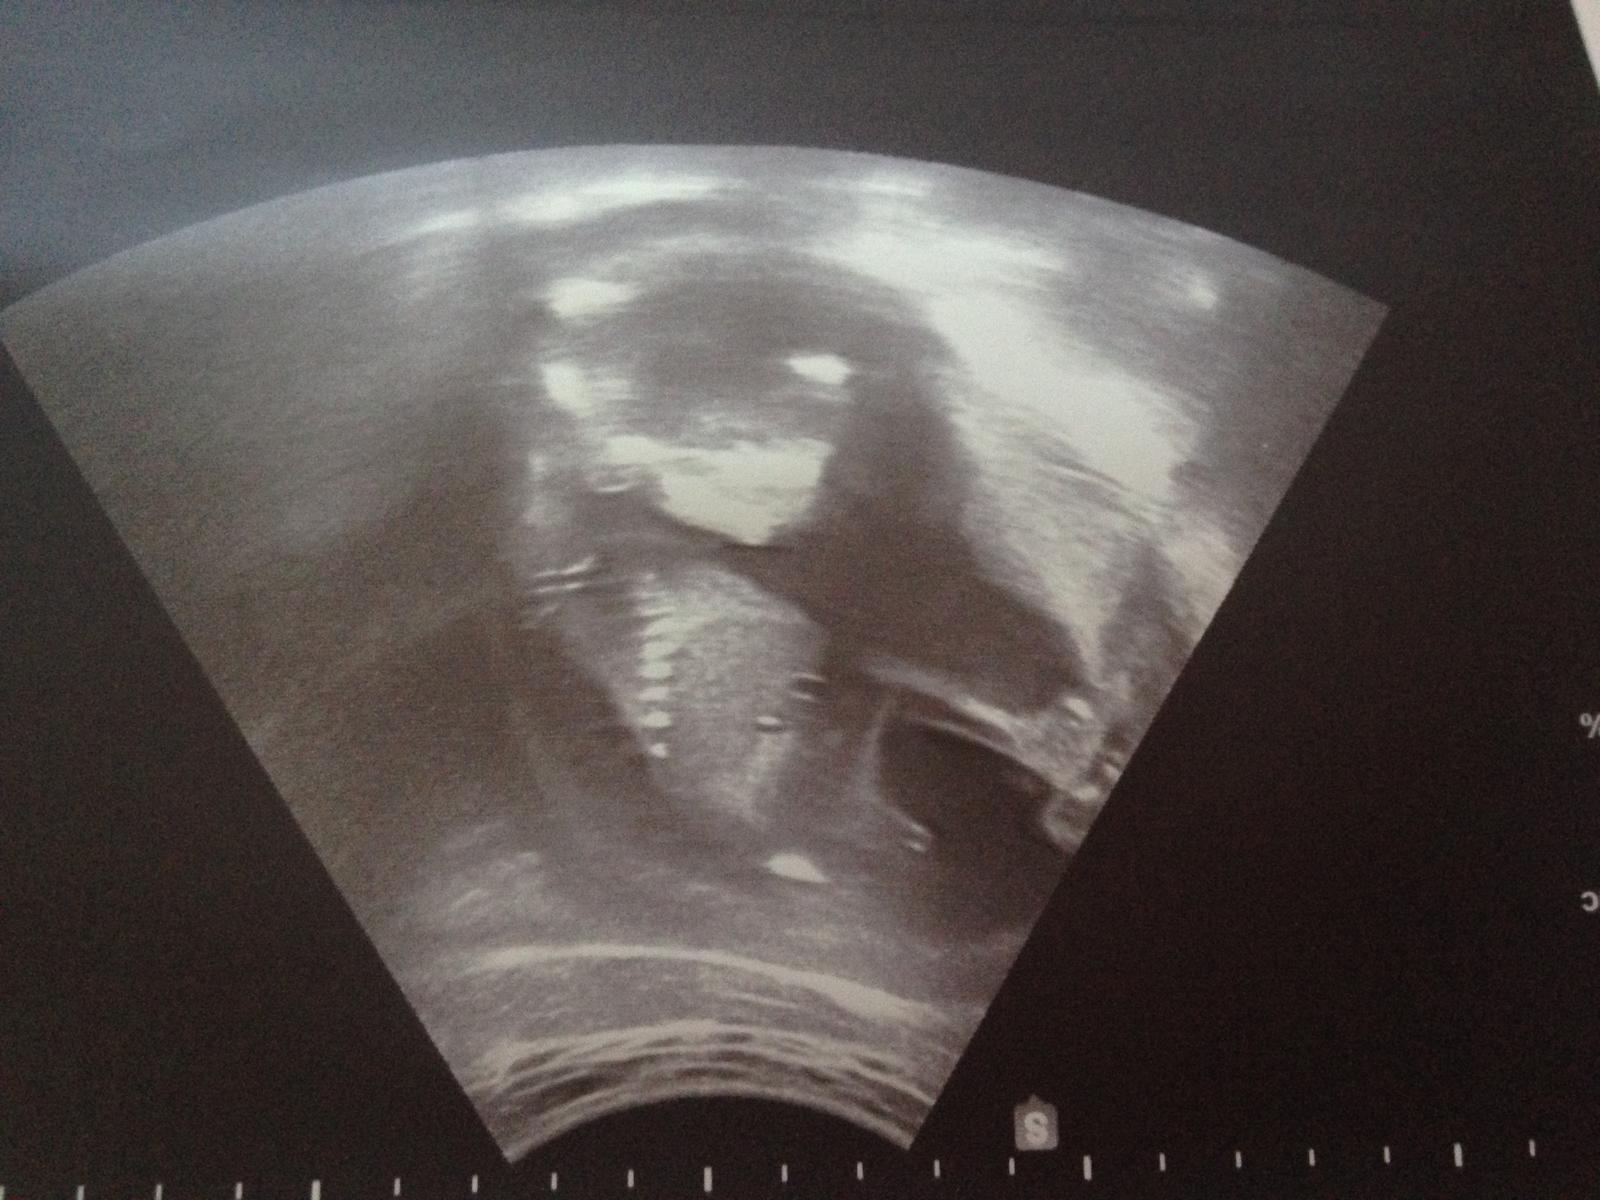

tak to jo - tak to vypadá vážně na chlapečka. Jak jsou hubený tak je maj prostě velký :D Kdyby to byla fotka z 12-13 tt tak by to vypadalo na holčičku (jednalo by se o pohlavní hrbolek který je rovnoběžný s páteří) ale v 17 to už bude pinďa , a mám dojem že vidím i varlátka.

(jinak jak je napsáno CRL tak to je kostrč - na druhé straně pak logicky hlava :D no a nad tím CRL ten výběžek o dvou jakoby čárečkách je ten pohlavní hrbolek na základě čeho se určuje pohlaví okolo toho 12 tt. )